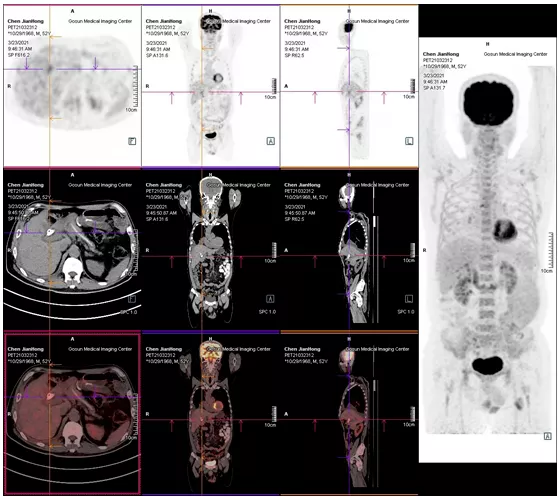

2021年05月 PET/CT檢查結果

復查PET-CT提示原術區復發病灶、肝內轉移灶、右側胸膜轉移灶控制良好

治療效果評估

用藥3個月后,患者精神狀態明顯好轉,食欲改善,體重增加,腫瘤指標下降,PET/CT結果提示,無明顯腫瘤復發或轉移征象,肝內腫瘤活性已受抑制。